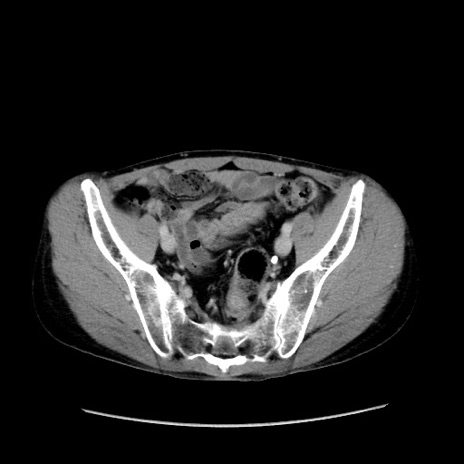

症例37(横断像)

【症例】40歳代 男性

【主訴】腹痛

【現病歴】4時間ほど前に電車に乗車中に臍部上より腹痛出現。徐々に増悪し起立困難となり、救急外来受診。生ものは数日食べていない。今朝お雑煮を食べた。

【身体所見】BT 36.8℃、BP 117/84mmHg、HR 91/min、SpO2 97%、苦悶様、腹部:臍上部広範囲圧痛あり、反跳痛±

【データ】WBC 8100、CRP 0.03